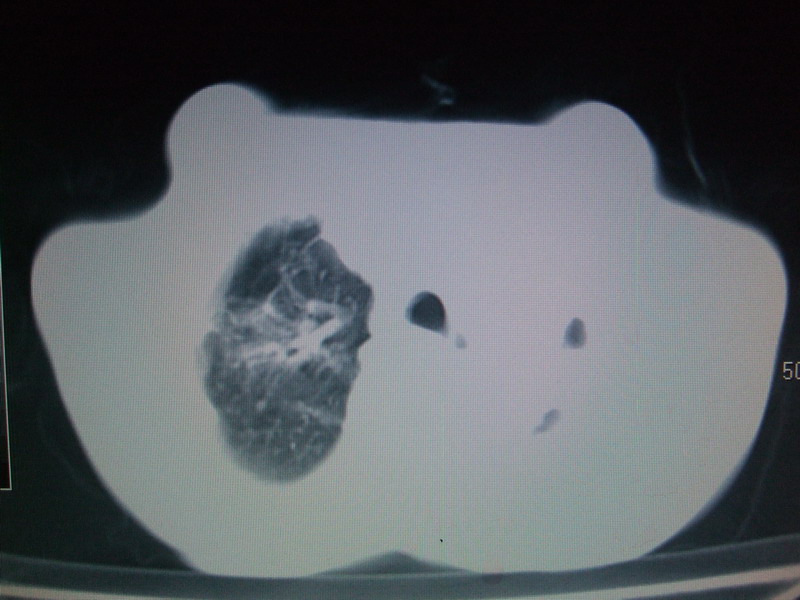

男  70岁,发烧咳嗽4天。盗汗,消瘦。无痰中带血丝,以前有肺tb病史,ct见,双肺tb,左侧胸廓塌陷,左胸膜肥厚粘连。纵隔移位,右侧胸腔积液,大家说说那个心影前左肺舌叶除了肺大炮还有炎症还是干酪性肺炎?有占位吗?我看纵隔淋巴结也大。

双肺继发性肺结核伴部分左肺毁损!

1)两肺继发性肺结核并左肺上叶肺不张,支气管扩张。2)双侧胸膜炎(胸膜增厚+少量胸腔积液)。